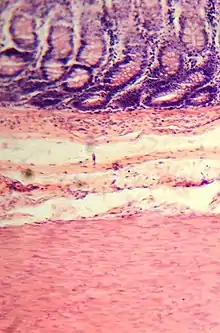

Microanatomy

Colonic crypts

The wall of the large intestine is lined with simple columnar epithelium with invaginations. The invaginations are called the intestinal glands or colonic crypts.

Micrograph of normal large instestinal crypts.

Anatomy of normal large intestinal crypts

The colon crypts are shaped like microscopic thick walled test tubes with a central hole down the length of the tube (the crypt lumen). Four tissue sections are shown here, two cut across the long axes of the crypts and two cut parallel to the long axes. In these images the cells have been stained by immunohistochemistry to show a brown-orange color if the cells produce a mitochondrial protein called cytochrome c oxidase subunit I (CCOI). The nuclei of the cells (located at the outer edges of the cells lining the walls of the crypts) are stained blue-gray with haematoxylin. As seen in panels C and D, crypts are about 75 to about 110 cells long. Baker et al.[31] found that the average crypt circumference is 23 cells. Thus, by the images shown here, there are an average of about 1,725 to 2,530 cells per colonic crypt. Nooteboom et al.[32] measuring the number of cells in a small number of crypts reported a range of 1,500 to 4,900 cells per colonic crypt. Cells are produced at the crypt base and migrate upward along the crypt axis before being shed into the colonic lumen days later.[31] There are 5 to 6 stem cells at the bases of the crypts.[31]

As estimated from the image in panel A, there are about 100 colonic crypts per square millimeter of the colonic epithelium.[33] Since the average length of the human colon is 160.5 cm[11] and the average inner circumference of the colon is 6.2 cm,[33] the inner surface epithelial area of the human colon has an average area of about 995 cm2, which includes 9,950,000 (close to 10 million) crypts.

In the four tissue sections shown here, many of the intestinal glands have cells with a mitochondrial DNA mutation in the CCOI gene and appear mostly white, with their main color being the blue-gray staining of the nuclei. As seen in panel B, a portion of the stem cells of three crypts appear to have a mutation in CCOI, so that 40% to 50% of the cells arising from those stem cells form a white segment in the cross cut area.

Overall, the percent of crypts deficient for CCOI is less than 1% before age 40, but then increases linearly with age.[30] Colonic crypts deficient for CCOI in women reaches, on average, 18% in women and 23% in men by 80–84 years of age.[30]

Crypts of the colon can reproduce by fission, as seen in panel C, where a crypt is fissioning to form two crypts, and in panel B where at least one crypt appears to be fissioning. Most crypts deficient in CCOI are in clusters of crypts (clones of crypts) with two or more CCOI-deficient crypts adjacent to each other (see panel D).[30]